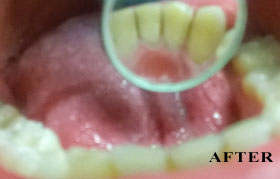

PHOTO GALLERY

Cosmetic, Reconstructive & Athletic Dental Surgeon - Smile Design / Implants